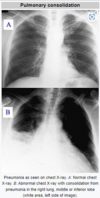

What is consolidation? (seen on xray in lung infections) How does it occur

Consolidation - region of normally compressible lung tissue - filled with liquid instead of air Happens as inflammatory fluid exudate accumilates in the alveoli and broncioles in acute inflammation MUST BE PRESENT IN ORDER TO DIAGNOSE PNEUMONIA - IT IS MORE RADIO OPAQUE - WHITER THAN NORMAL LUNG TISSUE